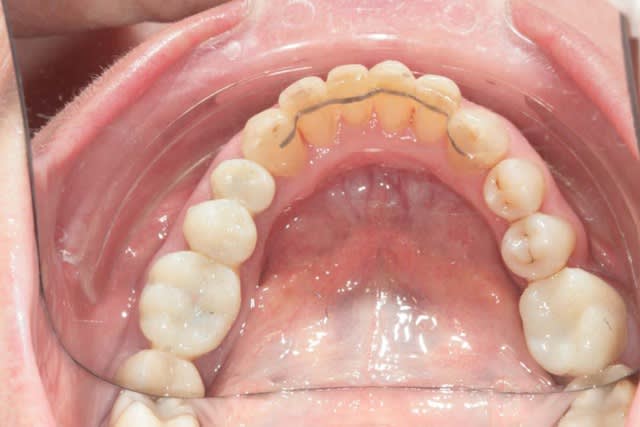

Voila la suite pour le maxillaire, le wax est fait sur arti en fonction de l'OIM obtenue après ortho. seule la 27 restera intacte.

Préparation des molaires pour permettre des RTE sous digue à travers les provisoires, retrait des anciennes couronnes et ancrages sur les 12, 15 et 25 endo satisfaisantes (couronnes ayant plus de 30 ans pour certaines!!!.

Tailles parallèles pour zircone 13 à 23 seront solidarisées pour éviter une migration post ortho.

Gingivectomie légère à la fraise à biseau pour harmoniser les collets, mais l'ortho a permis d'énormément faciliter ce travail.